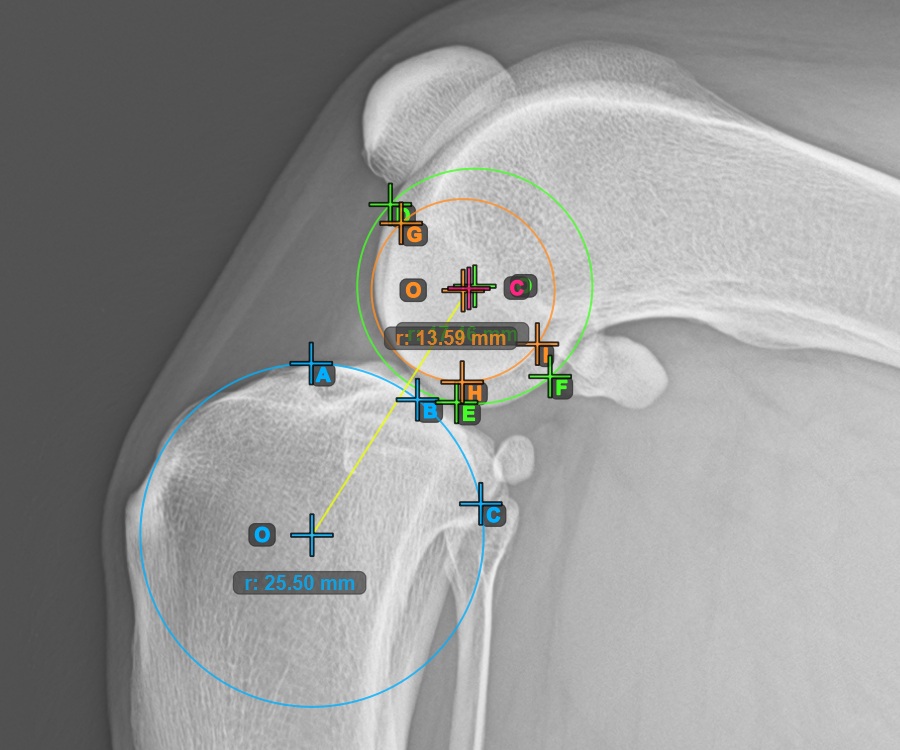

Additionally, mark the three points on the articular surface of the second Condylus Femoris.

Mark the three points on the inner (secondary) condylus of the femoral bone (Condylus Femoris). Regardless of the order, make sure to mark the most cranial point, the most caudal point and the midpoint of the Condylus Femoris. A circle will be automatically constructed based on the three placed points.

The image below represents a typical placement of the three points on the second Condylus Femoris.